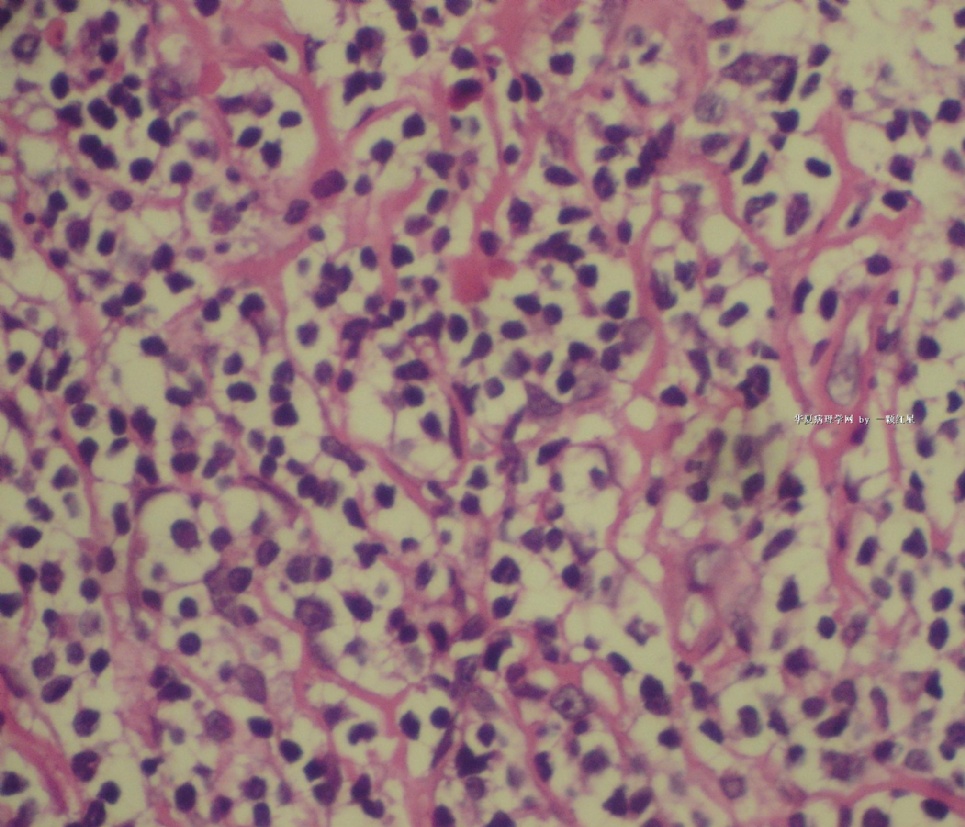

标本名称:  左前臂数个大小不等的皮下肿物。

既往有非何杰金淋巴瘤(滤泡性淋巴瘤)病史22个月。

• 左前臂数个大小不等的皮下肿物     淋巴瘤?图4

图4

病例不错。细胞胞浆透亮,间质血管丰富,图片不是很清晰,似乎有嗜酸粒细胞?

恶性,首先考虑T-NHL。IHC证实。

既往有NHL病史,图片不太清晰,细胞弥漫,胞浆透亮,首先考虑T细胞淋巴瘤。